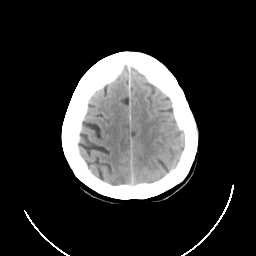

CT Study #3 -- Slice #23